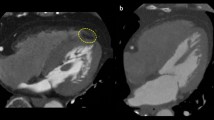

As a metric of fibrosis in the liver, liver stiffness was measured using 3D magnetic resonance elastography (MRE). The procedure was performed as previously described [17]. In short, an active electrodynamic transducer at 56 Hz was used, positioned to the right of the xiphoid process on the anterior chest wall, and held firmly in place using a broad elastic band. From four breath holds, a 3D image was acquired with nine slices, each with a slice thickness of 4 mm. Mean shear stiffness was determined using the KIR-software (for 3D processing), originally described in [18], and the results were reported in kPa. Regions of interest for the ROI measurements were defined away from large vessels and organ edges and drawn in the right liver lobe. See Fig. 1 for an example liver MR (magnetic resonance) elastogram.

A Liver elastogram from magnetic resonance elastography (3D MRE) in a 53-year-old male in the diabetes group, with a liver shear stiffness of 2.2 kPa. The position of the external transducer on the right anterior chest wall and the axial waves are schematically illustrated. The region of interest (ROI-2) for measurement of shear stiffness, located in the right liver lobe, is shown in blue (dashed). The larger region of interest (ROI-1) for defining the input region to the KIR-software is shown in orange (dotted), and the coloured overlay shows the result of the calculation within the region representing liver, on a background anatomical image. The image is presented using radiological convention. B Liver proton spectra from magnetic resonance spectroscopy, used for proton density fat fraction (PDFF) calculation, with water (H2O) resonance at 4.76 ppm and major fatty-acyl chain (-CH2-) resonance at 1.21 ppm

Spectroscopy

Liver proton density fat fraction (PDFF) was measured using magnetic resonance spectroscopy (MRS), as described in previous publications [16, 19, 20]. In short, data was acquired with a 1H-MRS PRESS sequence and subsequently post-processed to quantify the integrals of water and fat resonance, using the jMRUI and AMARES algorithms, respectively [21, 22]. Regions of interest of 30 × 30 × 30 mm3 were placed in the right liver lobe, in an area free from major blood vessels. All resonances from different lipid moieties were included in the spectral analysis. See Fig. 1 for an example liver spectrum from the MRS sequence.

A 3D cine balanced steady state-free precession sequence was used to assess LV structure (mass, end-diastolic volume, concentricity) and function (ejection fraction, stroke volume). Images were acquired during breath hold and subsequently post-processed by a reader (CE) with five years of cardiac imaging experience using Segment CMR version 3.2 R8452 (Medviso AB) [23]. LV mass was acquired in end-diastole, and the papillary muscles were regarded as part of the blood pool. LV concentricity was calculated as the ratio between LV mass and LV end-diastolic volume. Cardiac MR has previously shown excellent reproducibility for LV mass and volumes [24]. Where applicable, the Mosteller algorithm [25] was used to index the LV parameters and left atrial volume to body surface area (BSA): BSA (m2) = (height (cm) × weight (kg)/3600)0.5. See Fig. 2 for example images from the cardiac cine sequence.